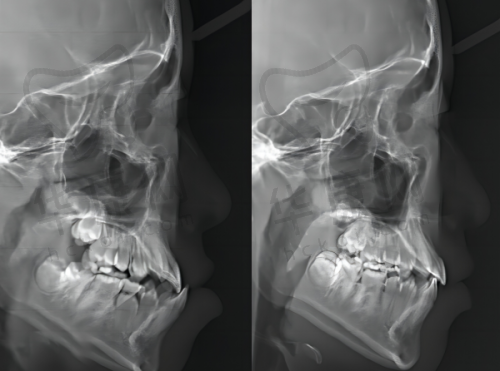

医院拥有众多成功的儿童正雅隐形矫正实例。例如,有一位12岁的儿童,牙齿存在重度的拥挤和不齐问题,经过成都西南口腔医院医生制定的正雅隐形矫正方案治疗后,牙齿逐渐变得整齐美观。在矫正过程中,孩子没有感到明显的不适,而且由于牙套的隐形成效,没有影响到他的学习和社交。经过一年多的矫正,孩子的牙齿达到了理想的矫正成效,家长对治疗结果非常满意。

这些成功实例不仅证明了成都西南口腔医院在儿童正雅隐形矫正方面的技术实力,也为更多家长和儿童提供了信心。